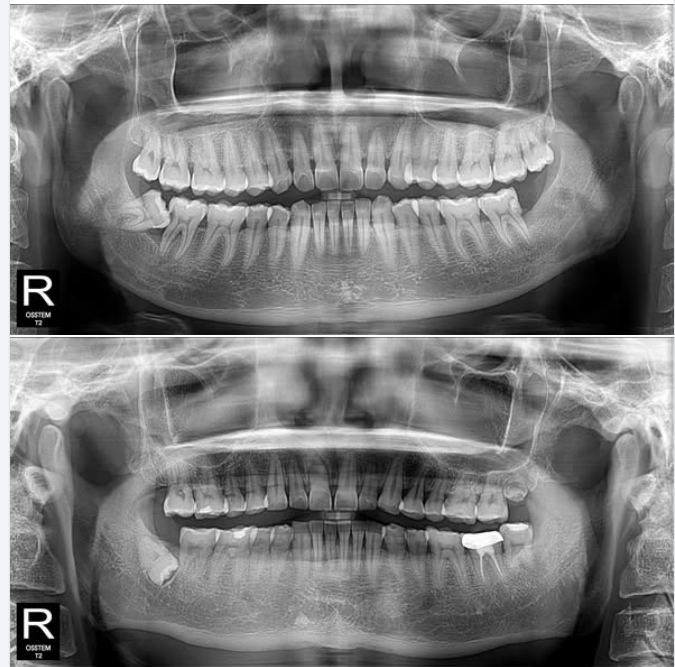

Nhổ răng khôn không đơn thuần là rút chiếc răng ra khỏi xương hàm, mà nó phức tạp hơn, đặc biệt nếu nó bị mọc kẹt.